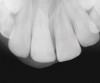

Figure 4  Clinical case of a lack of coronal seal that contributed to the failure of this root canal treatment.

Figure 4

Figure 5  Retreatment of the case shown in Figure 4.

Figure 5